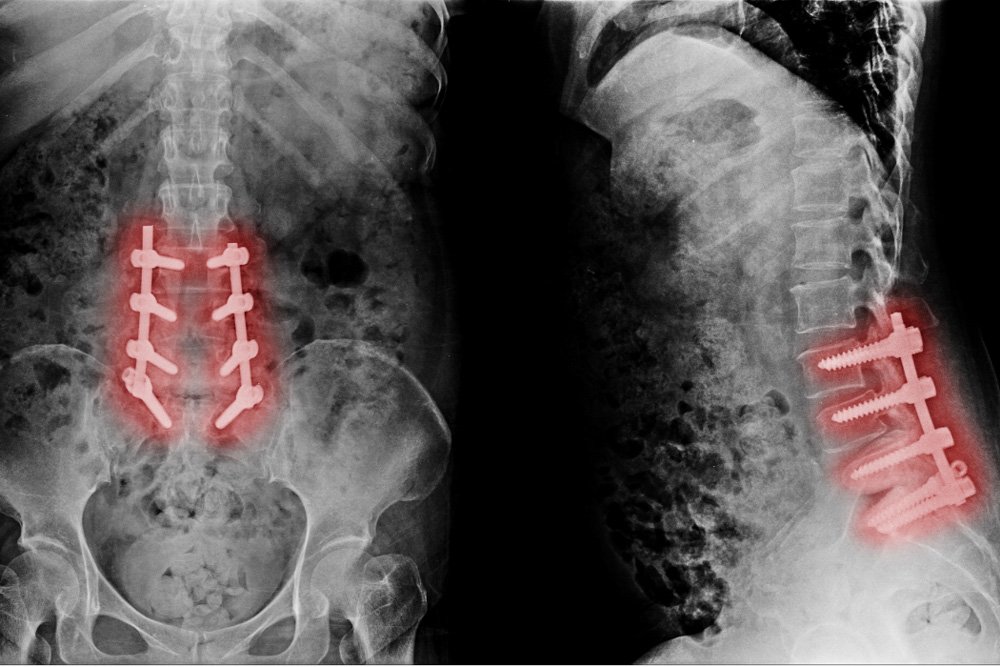

Artrodese de Coluna Vertebral

A Artrodese de Coluna é uma cirurgia que consiste na fixação da coluna vertebral indicada principalmente em situações em que haja uma instabilidade entre as vértebras, condição que causa dores, especialmente na realização dos movimentos.

Pacientes com fraturas, hérnia de disco, escoliose e muitas outras condições podem se beneficiar da técnica que pode ser realizada também de maneira minimamente invasiva.

Uma rápida recuperação pós-operatória, com retorno precoce às atividades de rotina e com menos dores durante a reabilitação são os principais benefícios.